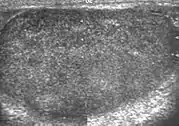

Testicular microlithiasis

Histologically, testicular microlithiasis refers to the scattered laminated calcium deposits in the lumina of the seminiferous tubules. These calcifications arise from degeneration of the cells lining the seminiferous tubules. At ultrasonography, microliths appear as tiny punctate echogenic foci, which typically do not shadow. Although minor microcalcification within a testis is considered normal, the typical US appearance of testicular microlithiasis is of multiple nonshadowing echogenic foci measuring 2–3 mm and randomly scattered throughout the testicular parenchyma [Fig. 25] (Dogra et al., 2003, as cited in Janzen et al., 1992). The clinical significance of testicular microlithiasis is that it is associated with increased risk of testicular malignancy, thus follow up of affected individuals with scrotal sonography is necessary to ensure that a testicular tumor does not develop.

Fig. 25. Testicular microlithiasis. Multiple hyperechoic foci without acoustic shadow presenting as a starry sky appearance is seen in the testis.